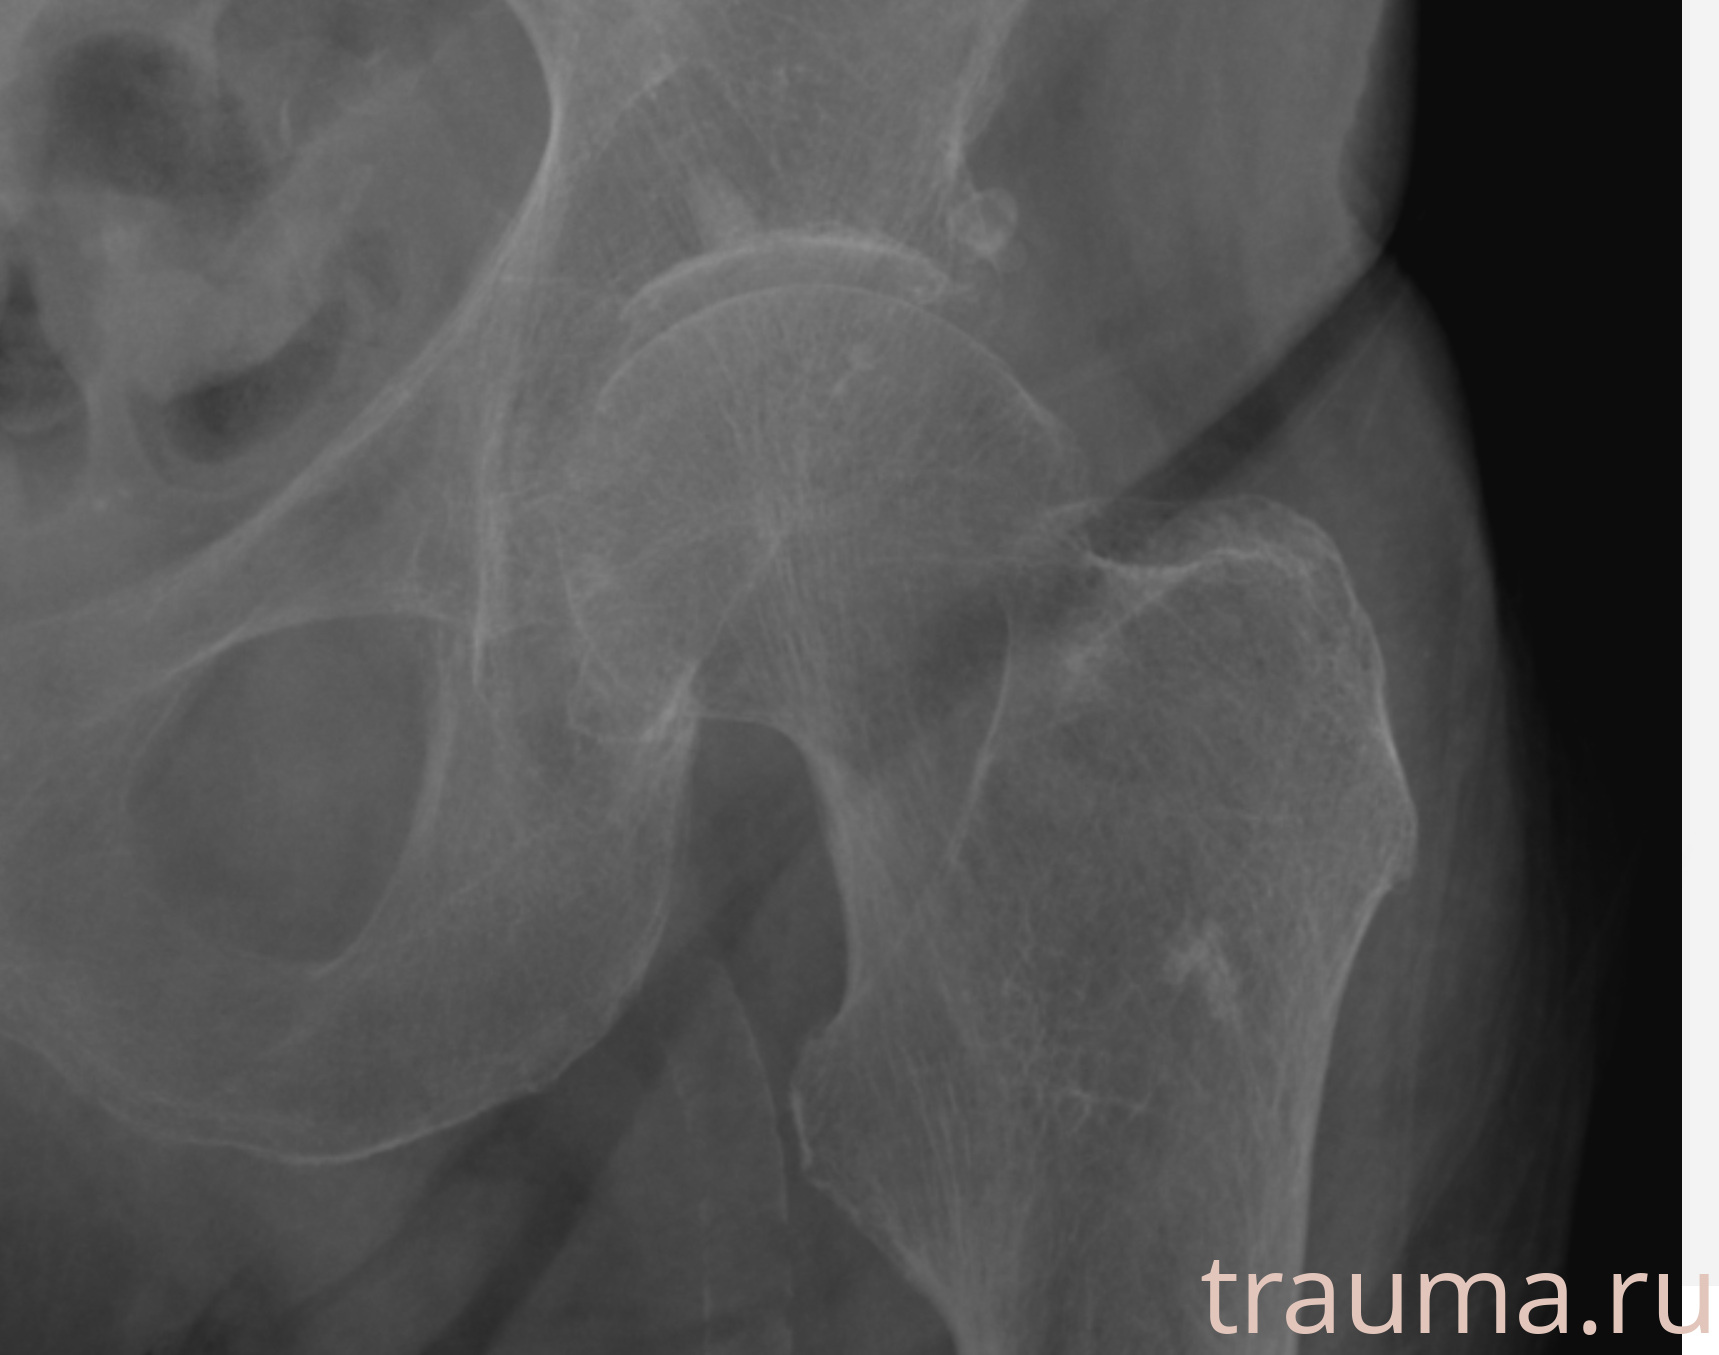

Первая помощь при переломе шейки бедра

Рентген на дому: по вашему адресу приезжает врач-рентгенолог, травматолог-ортопед с мобильным рентгеновским аппаратом, проводит диагностику травмы или заболевания, делает необходимые рентгенограммы, дает рекомендации по дальнейшему лечению. Получить качественные снимки в домашних условиях возможно благодаря уникальной методике, разработанной МосРентген Центром для института  Склифосовского